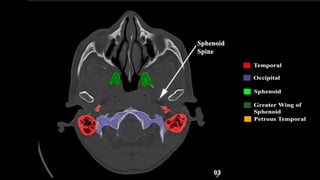

Pseudo-fractures

Extrinsic Fissures &

Sutures